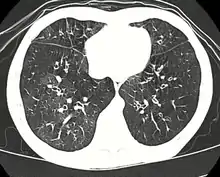

High-resolution CT scan of a child with post-infectious bronchiolitis obliterans showing glass pattern with air trapping and bronchial thickening

Typically found in young children and is the most common cause at this age.[31] Generally occurs after a viral infection of adenovirus (types 3, 7, and 21), measles (rubeola), mycoplasma, CMV, influenza, and parainfluenza.[4][6] Swyer-James syndrome is a rare complication of bronchiolitis obliterans caused by measles or adenovirus.[32] Post-infectious bronchiolitis obliterans is most common in the southern hemisphere particularly in countries such as Brazil, Argentina, Australia, Chile and New Zealand.[33] There was a large prevalence of the disease in these areas during the 1990s and early 2000s. In one hospital in Buenos Aires, the Ricardo Gutiérrez Children's hospital, the disease accounted for 14% of their inpatient respiratory population from 1993 to 2002.[33] As such, much of the information about post-infectious bronchiolitis obliterans has come from research out of South America. The most significant risk factors for the disease are infection with adenovirus and the need for ventilator support.[33] In contrast with another cause of bronchiolitis obliterans in children, Steven's Johnson's syndrome, post-infectious bronchiolitis obliterans tends to be a chronic but non-progressive disease.[31] The disease can have varying impact on children and their quality of life, which has been studied by lung function tests, as well as their exercise tolerance.[34] Children with lower lung function based on their pulmonary function testing, have lower exercise tolerance, which compounds the impact of the disease on cardiovascular function as they are not able to maintain age appropriate aerobic fitness.[34] This ultimately affects their activities of daily living (ADLs) and their quality of life going forward.[34]